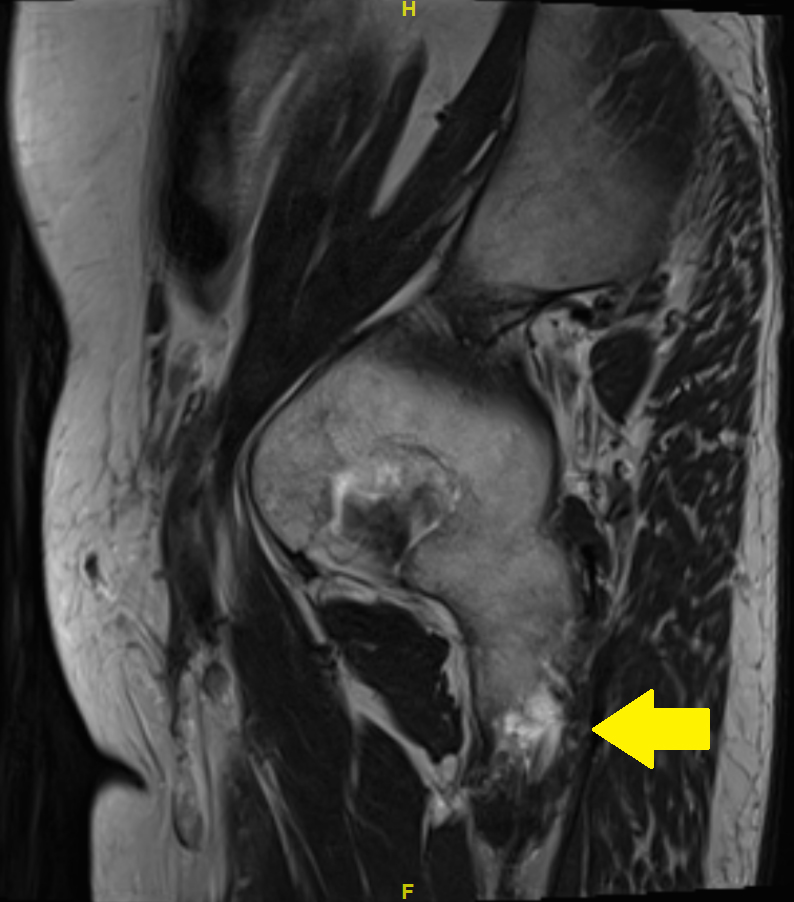

Because of a nonresponse to these measures, magnetic resonance imaging (MRI) of the pelvis was carried out. The MRI showed complete bilateral avulsion of the proximal hamstring muscles with the exception of some remaining fibres of the long head of the biceps femoris muscle on the right side (figs 1—4). There were no clear signs of inflammation nor any signs of myxoid degeneration. Also, there were no signs of inflammation in the area of the hamstring tendons in a past positron emission tomography-computed tomography (PET-CT) performed for melanoma follow up 4 months prior to the MRI.

Figure 3 MRI of the pelvis with T2 turbo spin echo (TSE) images: sagittal view. Arrow: partial avulsion on the right side.